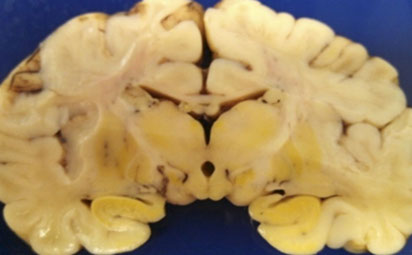

Machiafava-Bignami disease (MBD)

Rare, demyelination of the corpus callosum; assoc c chronic alcoholism

- rarefied corpus callosum, and some reactive changes

- originally described in Italian men that were drinking lots of red wine, that got hemorrhage into corpus callosum

Marchiafava-Bignami disease